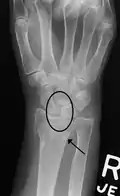

X-ray images indicate scapholunate ligament instability when the scapholunate distance is more than 3 mm, which is called scapholunate dissociation.[7] A static scapholunate instability is generally readily visible, but a dynamic scapholunate instability can only be seen radiographically in certain wrist positions or under certain loading conditions, such as when clenching the wrist, or loading the wrist in ulnar deviation.[6]

Static scapholunate dissociation -